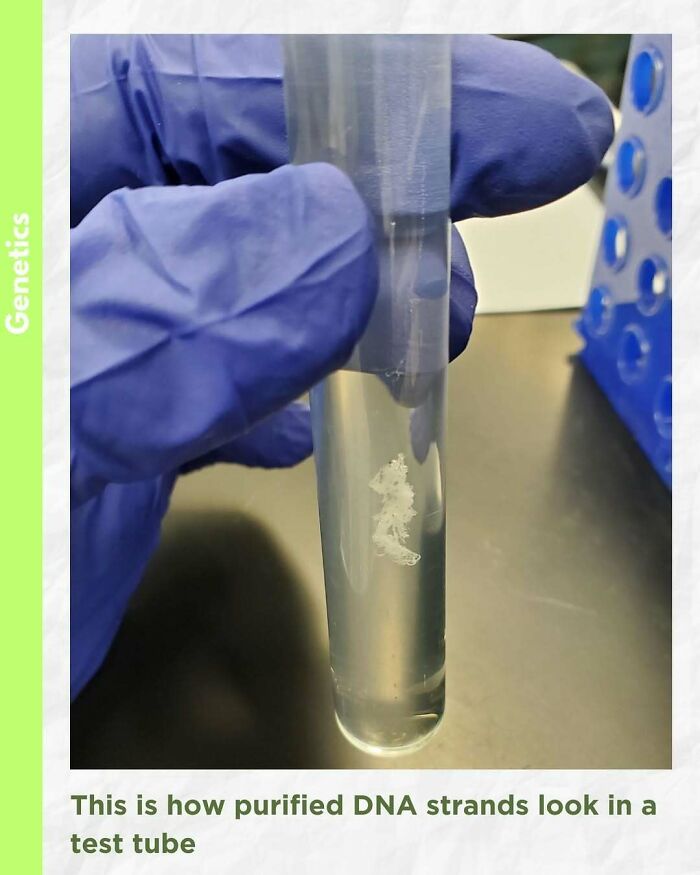

Fascinating to see purified DNA (Deoxyribonucleic acid) inside a test tube

In today’s world of DNA analysis by multiplex and real-time PCR, the importance of high-quality, purified DNA cannot be underestimated. Finding a suitable DNA isolation system to satisfy your downstream application needs is vital for the successful completion of experiments.

There are five basic steps of DNA extraction that are consistent across all the possible DNA purification chemistries: 1) disruption of the cellular structure to create a lysate, 2) separation of the soluble DNA from cell debris and other insoluble material, 3) binding the DNA of interest to a purification matrix, 4) washing proteins and other contaminants away from the matrix and 5) elution of the DNA